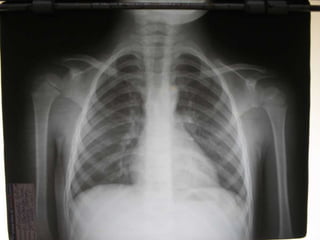

•Edad 6 años

•Tos de 1 año

•Falta de apetito

•PPD: 10 mm

Criterios Radiológicos

• Permite evidenciar la presencia,

extensión y localización de la lesión en

pacientes con sospecha de TB

• En la Tb miliar puede hacer el

diagnóstico

• Es de mucha ayuda en el derrame

pleural tuberculoso

• La tuberculosis extrapulmonar tiene

radiografías de tórax normal